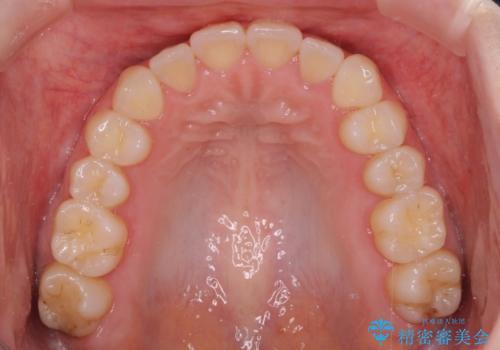

前歯のクロスバイトをインビザライン矯正で改善

- 前歯のデコボコと上下のクロスバイトを気にして来院された患者様です。

インビザラインを用い、IPR(歯と歯の間を削る)と歯列全体を拡大させることで、歯並びを整えていくこととしました。

上の前歯が下の前歯を乗り越える際、奥歯がほとんど咬めない時期があり、乗り越えた後も、インビザライン特有の奥歯の咬みにくさが続きました。

咬み合わせ改善のために治療期間を要しましたが、最終的に奥歯はしっかりと咬めるようになりました。